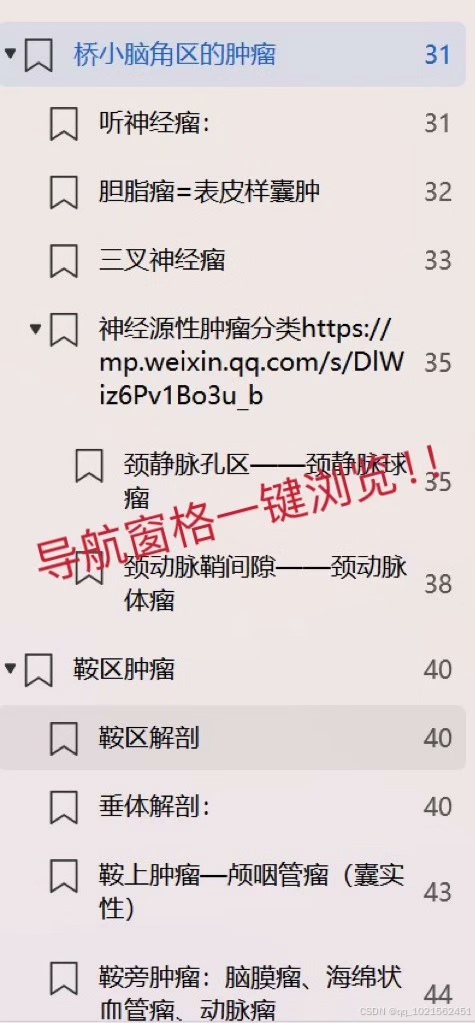

规培结业考试已通过,现分享自己花了大量时间和精力根据考点做的重点笔记,里面包含实际病例影像图片帮助记忆,横向和纵向鉴别诊断表格等,适合看不下去教材,没时间梳理和总结重点的朋友。

这本笔记分为了7个部分:神经系统,头颈,呼吸系统,心血管系统,消化系统,泌尿生殖系统和骨关节系统。平均每个系统2块多

笔记来源:最初是为了研究生复试,收集了各个院校的笔试大题和面试专业题题干,然后根据教材的知识点,辅以各种其他书籍、专业公众号整理的答案,这里面不是单纯知识点的罗列,而是结合了实际考题进行了有逻辑的梳理,里面有很多鉴别诊断的表格,还有思维导图。最后背了自己整理的资料,考研面试成绩第一。后面在规培的过程中根据规培大纲和日常写报告的经验,又如法炮制,进一步完善了这份笔记,在规培结业考试的时候就直接省去了看教材这个过程,为我大大提升了效率,缩短了复习时间!!!!